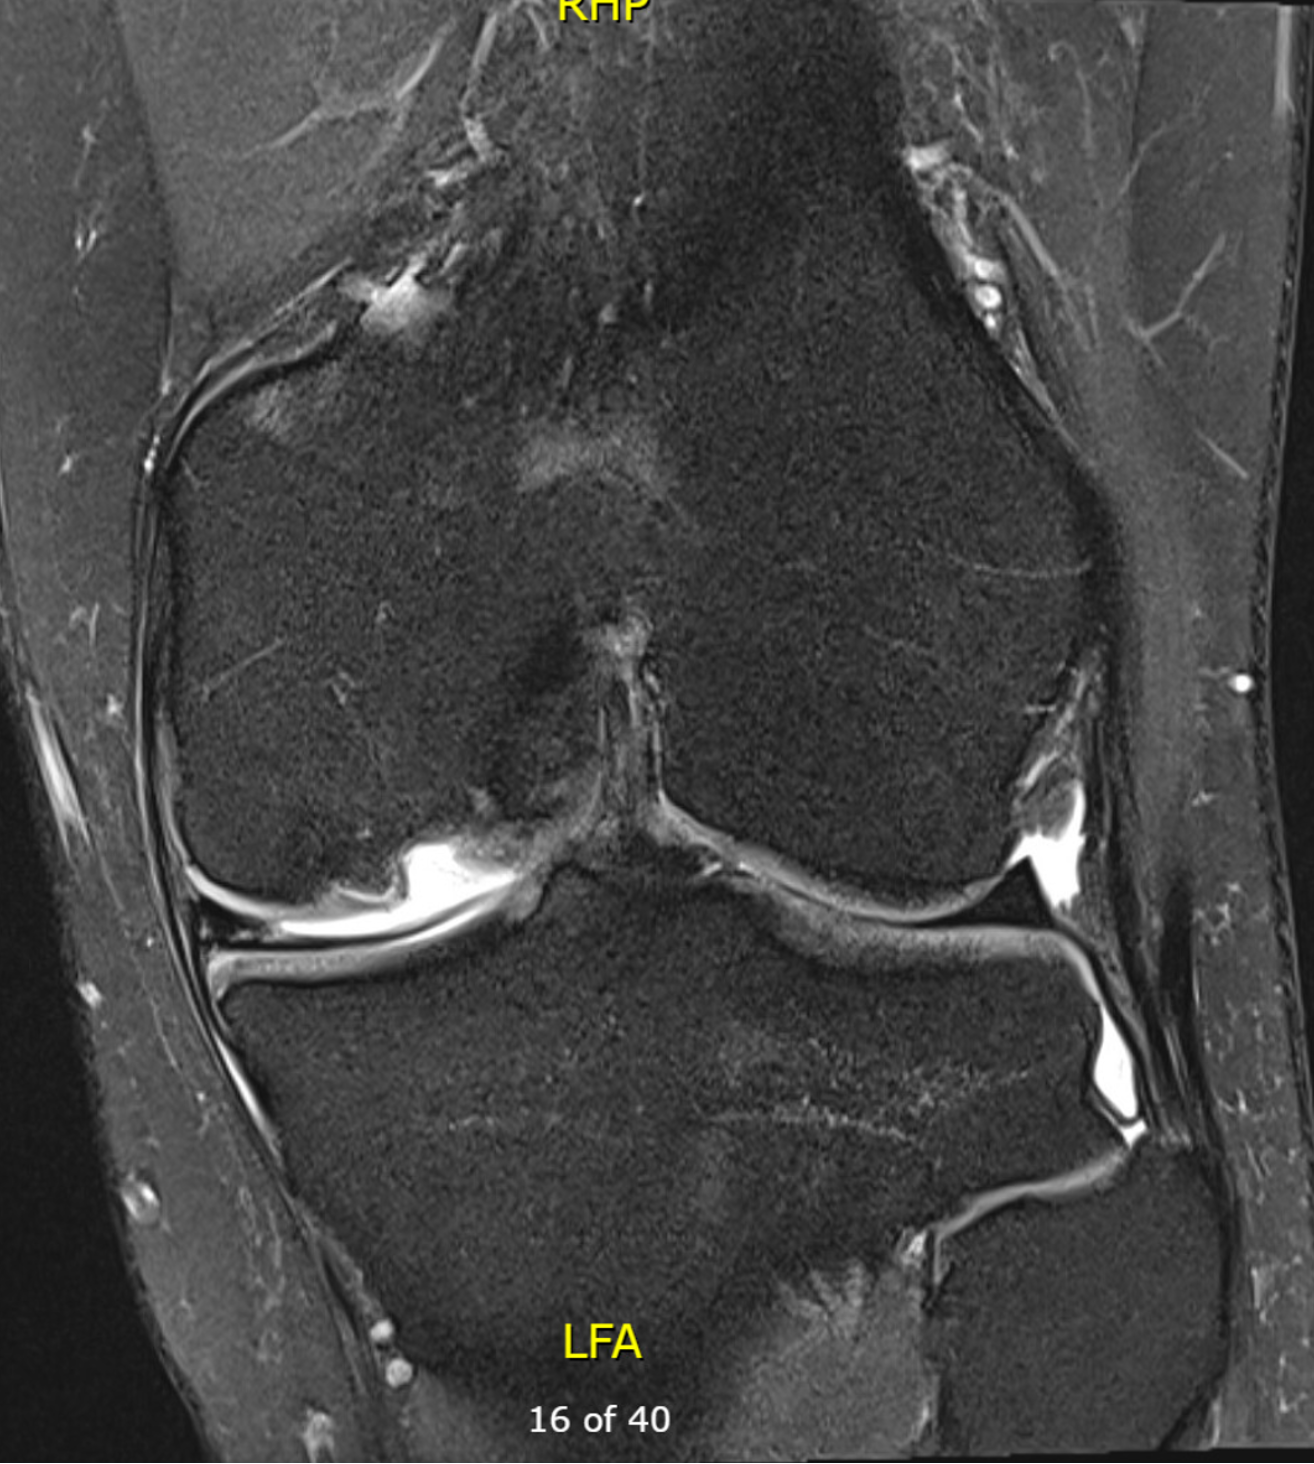

MRI

Chondral defect

Osteochondral defect